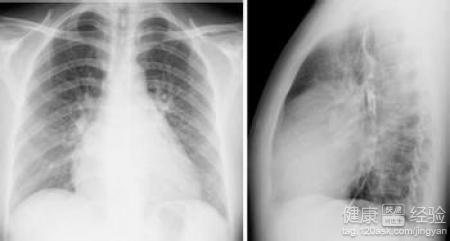

風濕性心髒病都有什麼樣的臨床症狀?

風濕性心髒病有的患者檢查出來的時候已經很嚴重了,就是因為其實症狀早就出來了,沒有引起足夠的注意,所以今天我就把風濕性心髒病的常見症狀總結出來。